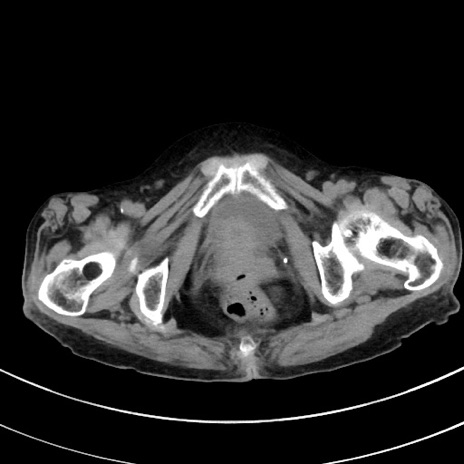

症例33(横断像)

【症例】70歳代 女性

【主訴】心窩部痛

【現病歴】延髄病変の精査・加療にて神経内科入院中。本日より心窩部痛あり。

【既往歴】虫垂炎

【身体所見】右下腹部を中心に圧痛と反跳痛あり。

【データ】WBC 10900、CRP 0.02